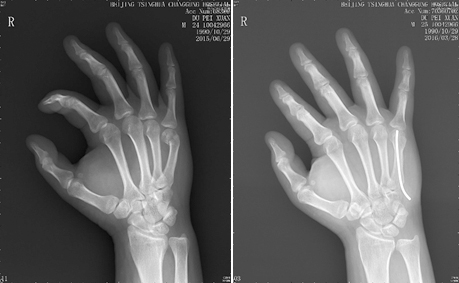

3、手足骨折的微创治疗:

手足部位的骨折,好发于青壮年劳动力,传统治疗方法采用切开复位钢板螺钉内固定,由于对软组织剥离大,神经血管损伤及术后肌腱粘连发生率高,造成术后手指活动不良甚至致残;且需要二次手术取出钢板螺钉,给患者恢复带来困难。而北京清华长庚医院创伤骨科中心应用独有的髓内针治疗该类骨折,做到了“不切开”——仅留一针眼,“不出血”——术中出血约1ml,术后功能康复效果良好。

第五掌骨骨折闭合复位髓内针治疗前后对比图,该手术仅通过一个针眼完成固定,实现“不切开”“不出血”的微创治疗。